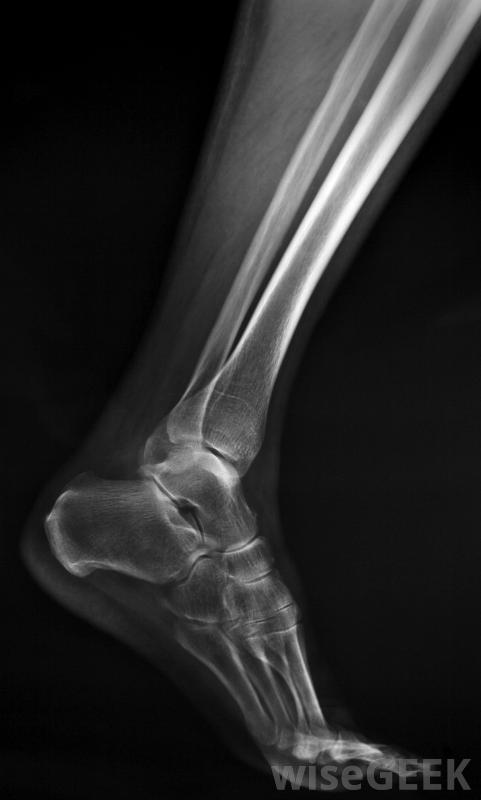

腓骨比胫骨更薄、更脆弱。

腓骨也被称为小腿骨之一,位于侧面或小腿外侧。这又长又细的骨头钩在胫骨上,从膝盖下一直延伸到脚踝。它与较重的邻近胫骨的连接方式使这两块骨头看起来像一个钩子或安全别针。虽然胫骨承受着身体的重量,并且在某种程度上独立于腓骨,但较粗的骨头发生骨折可能会同时损伤腓骨。腓骨不能承受重量,固定腓骨板可为该骨提供必要的额外支撑,以确保正常愈合。